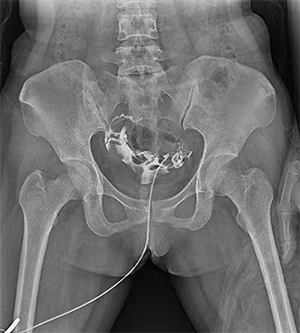

PLD6500系列是普利德研发的医用数字X线摄影机,采用双立柱结构,可供各级医院放射科对头部、胸部、腹部、腰椎、四肢等部位进行立位、卧位、正位、侧位的数字摄影检查。